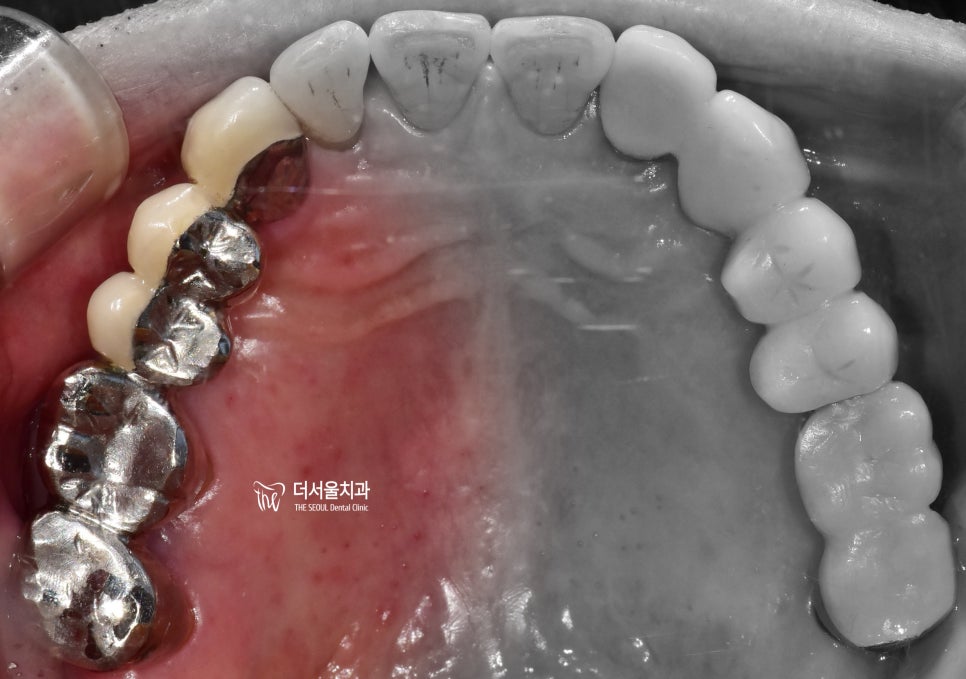

정면에서 봤을 때는 구강 내 전체적으로,

치은 퇴축이 심하다는 것을 볼 수 있습니다.

블랙트라이앵글 형성 및

잇몸이 아래로 내려감에 따라서

치아의 치경부(cervical)쪽이

다 드러나 있는 상황이네요.

교합면에서는 크게 잘못 된 느낌을

받을 수 없죠?

하지만, 그 아래에서는 이미

염증 및 골 소실에 따라서 치아들이

생활력을 잃어가고 있는 중이였습니다.

근데, 과거 타 원에서 만들어둔 보철의

형태를 보면.. 뭔가 잘못 된 느낌입니다.

마진도 하나도 안 맡고 환자의

구강 내 환경에 어울리지 않게

크라운을 만들어드렸던 것이

또 하나의 원인이 되는 느낌입니다.